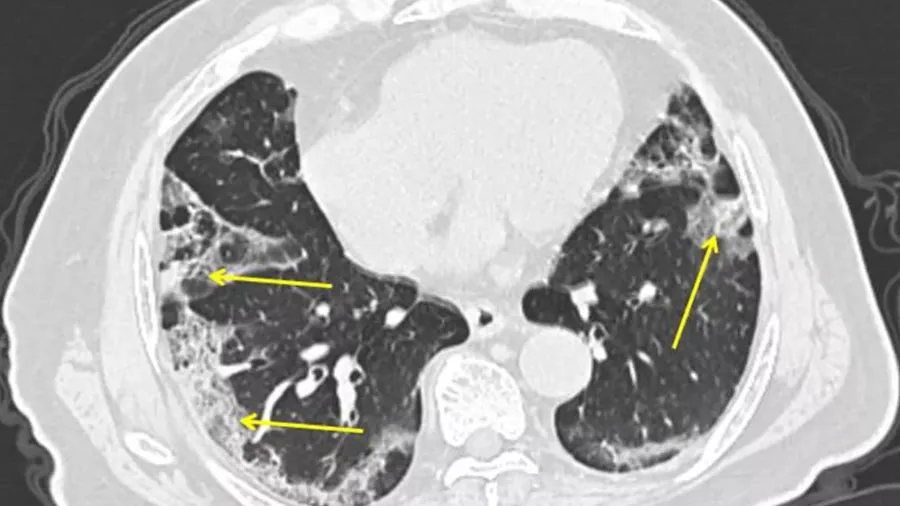

ચીનના નેશનલ હેલ્થ કમિશનમાં મેડિકલ પોલિસી અને એડમિનિસ્ટ્રેશનના ડેપ્યુટી હેડ જિયાઓ યાહુઈ કહે છે કે વ્હાઇટ લંગ્સ એ ન્યુમોનિયાનું વધુ ગંભીર સ્વરૂપ છે, જેમાં સફેદ ઈમેજ એરિયા દર્દીના ફેફસાના 70 થી 80 ટકા સુધી પહોંચે છે. તેમણે એમ પણ કહ્યું કે આવા લક્ષણો ધરાવતા દર્દીઓનું પ્રમાણ ખરેખર ઘણું ઓછું છે.

ચીનમાં એવા સમાચાર સામે આવ્યા છે કે આ વખતે કોરોના સંક્રમિત કેટલાંક દર્દીઓમાં વ્હાઇટ લંગ્સના લક્ષણો જોવા મળ્યા છે. આ નવા અહેવાલને કારણે ચીનની ચિંતા વધી ગઇ છે. ગ્લોબલ ટાઇમ્સના અહેવાલ મુજબ ચીનના સોશિયલ મીડિયા પ્લેટફોર્મ પર કેટલીક પોસ્ટ વાયરલ થઇ ગઇ, જેમાં દાવો કરવામાં આવ્યો છે કે ઉત્તરી ચીનના હેબેઇ પ્રાંતમાં કેટલાંક કોરોના પોઝિટિવ દર્દીઓનો સીટી સ્કેન કરવામાં આવ્યા તો તેમનામાં વ્હાઇટ લંગ્સ જોવા મળ્યા. વાયરલ પોસ્ટમાં એવો દાવો કરવામાં આવ્યો છે કે વ્હાઇટ લંગ્સ મળવાનો મતલબ એ વાતનો સંકેત છે કે એ દર્દી ઓમિક્રોન વેરિયન્ટથી સંક્રમિત નથી, પરંતુ વુહાનમાં જોવા મળેલો ડેલ્ટા વેરિયન્ટથી સંક્રમિત છે. એનો મતલબ એ થાય છે કે ચીનમાં ફરી એકવાર વુહાનથી નિકળેલો જૂનો ડેલ્ટા વેરિયન્ટ લોકોને સંક્રમિત કરી રહ્યો છે.